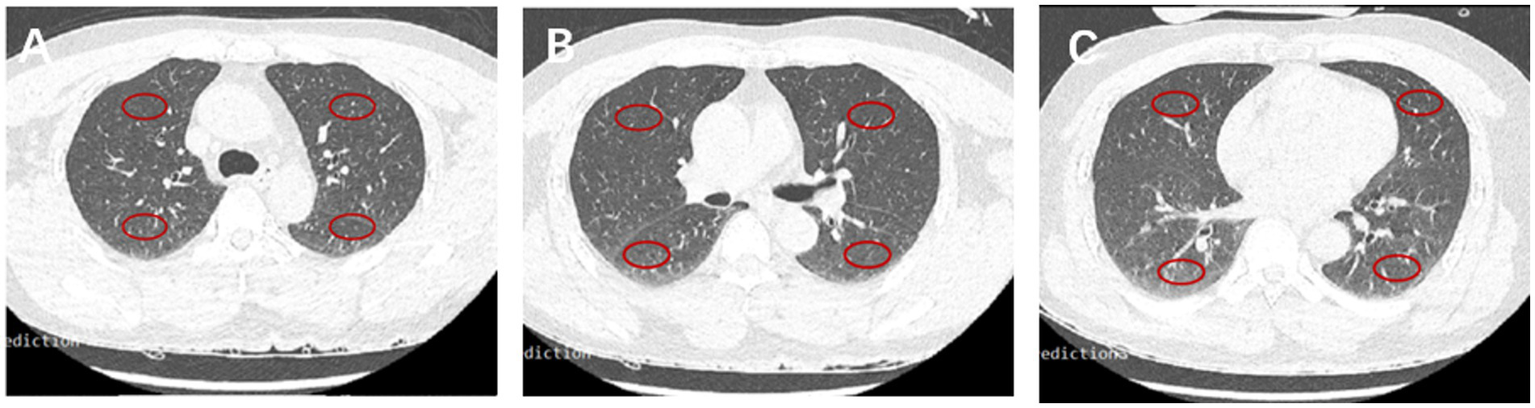

The imaging features of the lungs related to hydrostatic changes and other signs were evaluated and recorded, including small ill-defined opacities, interlobular septal thickening, ground-glass attenuation, airspace consolidation, and pleural effusion (Figure 1) (15). For quantitative analysis, we used the sector method to measure the density of a peripheral area of lung parenchyma (16, 17). We manually drew regions of interest (ROIs) on the axial images in 12 regions, including the right and left upper lobes, left lingula and right middle lobe, and left and right lower lobes (size, 2 cm × 1 cm), and recorded CT Hounsfield unit (HU) of every ROI. The central vasculature, including the main and lobar pulmonary arteries, pulmonary veins, and airways, were excluded from the ROIs (Figure 2). The mean anterior/posterior lung density ratio (ΔA/P) for the patients was determined as follows: the density values in the ROIs at the peripheral one-third of the right and left anterior and posterior lung fields were arithmetically averaged.

Figure 2

CT HU in 12 fields of the lung. Representative ROIs in different lobes in the carina (A), main stem bronchi (B), and bottom (C) levels.